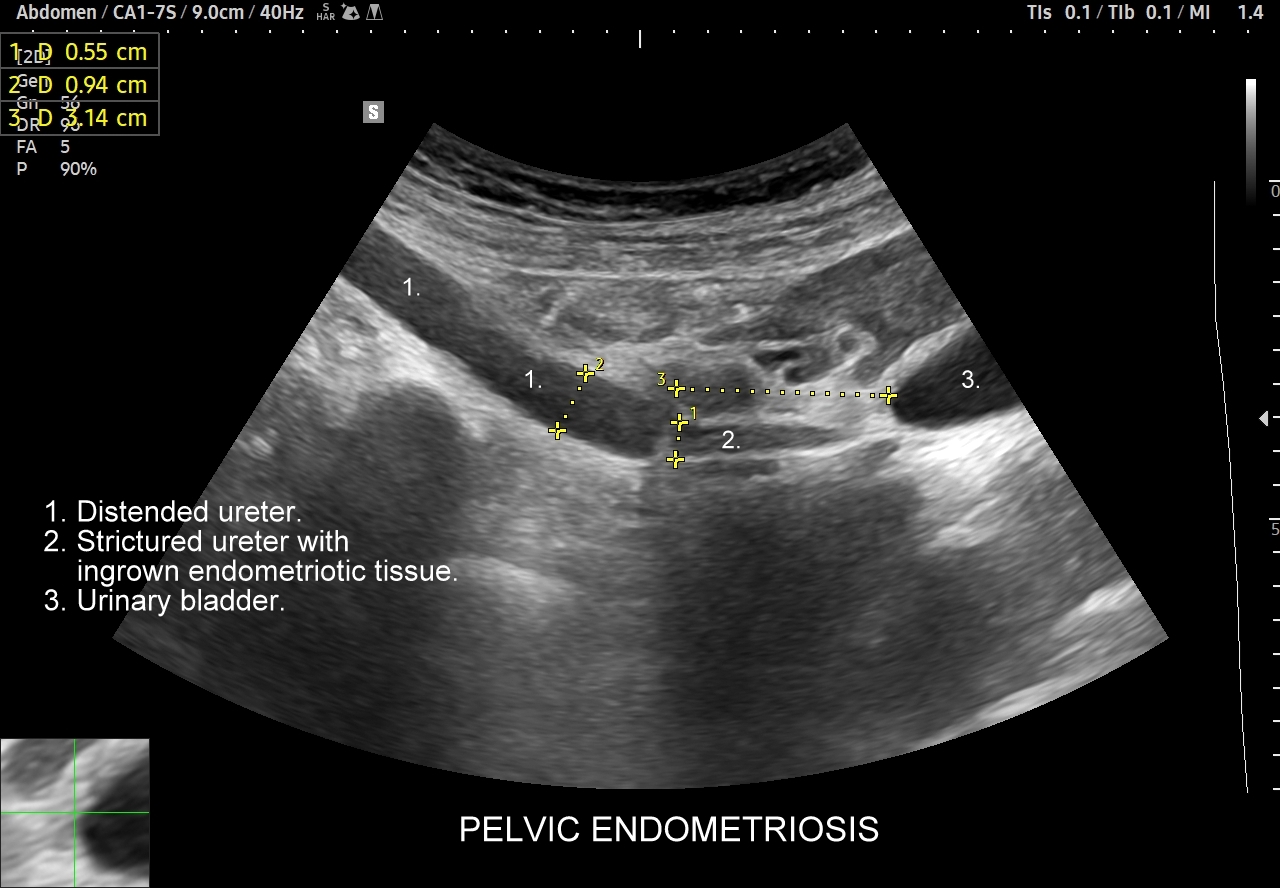

W badaniu USG ogniska endometriozy zwykle przyjmują formę hypoechogennych guzków i nieregularnych mas; mogą być niejednorodne echogenicznie i zawierać drobne obszary torbielowate; w trybie color-Doppler i MVI wykazują skąpe unaczynienie.

Na skanach w niniejszym artykule zaprezentowany jest przypadek endometriozy głębokiej w miednicy mniejszej z intraluminalnym nacieczeniem dystalnego odcinka moczowodu, jego całkowitą niedrożnością i wtórnym wodonerczem. Choroba w tak zaawansowanym stadium wykryta została przypadkowo w rutynowym przezbrzusznym badaniu USG jamy brzusznej. W ramach diagnostyki różnicowej przeprowadzone zostały badanie CT, MRI oraz ureterocystoskopia z pobraniem materiału do badania histopatologicznego, na podstawie którego postawiono rozpoznanie endometriozy.